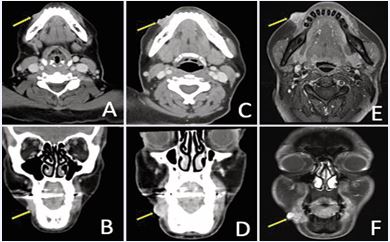

Three years later, serial imaging demonstrated increased thickening and enhancement along the right temporalis fascia. These findings continued to progress over the next six years with several enlarging subcutaneous nodules, which ultimately coalesced into a painful, 6 cm multilobular lesion along the right temporal scalp abutting the temporalis muscle and extending to the cutaneous surface without bony invasion, as demonstrated on contrast-enhanced head CT (Figure 1).

Figure 1 Contrast-enhanced CT head demonstrating right temporal scalp recurrence in A) coronal; and B) axial planes.

A 62-year-old woman with a history of ACC of the right parotid gland was initially treated with right deep lobe parotidectomy, which revealed pT3 disease with perineural invasion and positive margins. She subsequently received adjuvant EBRT (60 Gy) with concurrent carboplatin and paclitaxel. Approximately nine years after definitive treatment, surveillance contrast enhanced neck MRI demonstrated interval enlargement of enhancing soft tissue in the right parotid bed lateral to the right masseter muscle, previously interpreted as post surgical change, now measuring 1.2 cm (previously 0.7 cm) (Figure 4A).

Figure 4 (A) Contrast-enhanced neck MRI demonstrating enlarging soft tissue enhancement in the right parotid bed, suspicious for local recurrence. (B) PET/ CT confirmed increased FDG activity associated with recurrence.

Fine-needle aspiration performed confirmed recurrent ACC. Positron emission tomography/computed tomography (PET/CT) obtained for staging revealed mild FDG uptake at the site without evidence of metastatic disease (Figure 4B).